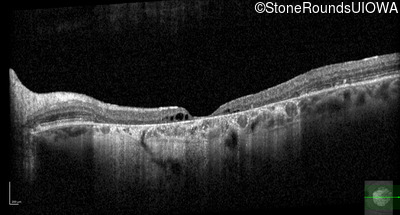

Optical Coherence Tomography - Right - 20/160 -1

Exemplar / OCT Stack

Optical Coherence Tomography - Left - 20/125